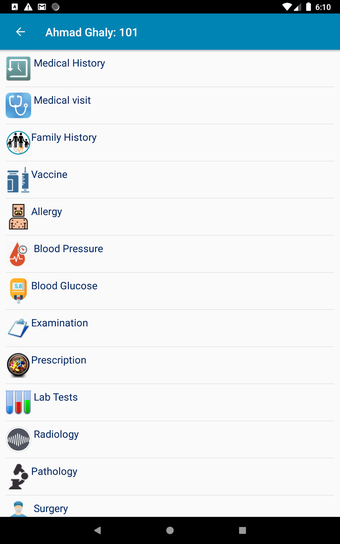

The Android Medical Records App by MedClin is a free medical records tracker app that allows users to store anamnesis, patient records, patient history, and health information. It is easy to use and provides numerous features such as username and password authentication, exporting medical data to Excel Sheet, and the ability to attach medical documents of any type. The app also has a smart search feature that allows users to search for patient information by name or ID, and even capture a photo for their profile.

In addition, the app has a blood pressure module that measures systolic, diastolic, and pulse, and allows users to export blood pressure reports to either PDF or graphs. The app also has a blood glucose (sugar) module that records blood sugar values and allows users to export blood glucose reports to either PDF or graphs. Users can also send blood pressure and blood sugar reports to their doctor. The app is compatible with multiple screens, including phones and tablets, and works on Chromebook systems. Overall, the Android Medical Records App is a great tool for patients and physicians alike for managing patient information and medical records.